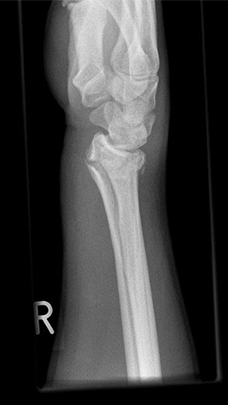

Radiusfraktur vor Korrekturoperation mit anhaltende beugeseitige Verschiebung der Handwurzel

Radiusfraktur vor Korrekturoperation: Die beugeseitige Knochenlippe ist über die liegende Platte hinweg verschoben.

Komplexe rechtsseitige Unterarm-Handgelenksfraktur

Komplexe rechtsseitige Unterarm-Handgelenksfraktur, seitlich